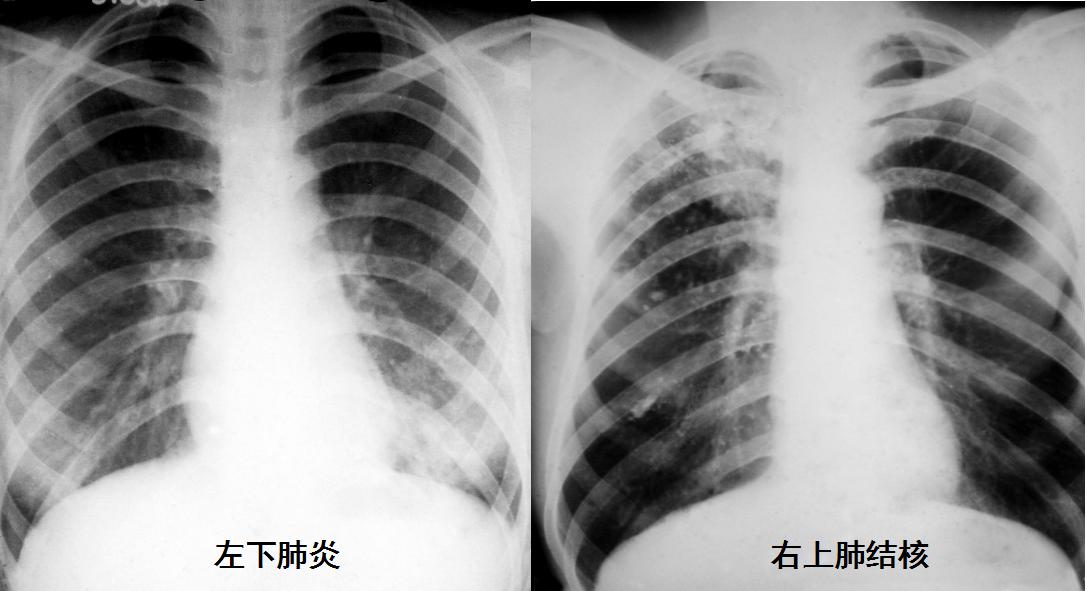

普通X线检查(通常就是指拍X光片)因操作简便、成像时间短、价格低廉、应用历史最长且技术成熟、整体观和空间分辨力强等优点,是最基本的影像学检查方法。最常用于骨关节、胸部、乳腺、消化道、子宫输卵管等部位或器官的检查。

一张胸片可以看到很多问题,整体观非常好